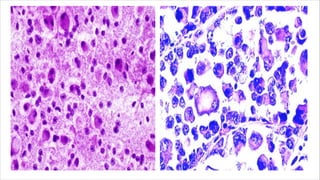

Clear cell sarcoma of soft tissue

• Malignant tumour composed of glycogen rich clear cells.

• Also termed as malignant melanoma of soft tissue parts.

• Share some features of clear cell sarcoma of GIT.

• Epithelioid to spindle cell morphology vesicular nuclei ,

prominent nucleoli & abundant clear cytoplasm.

• Multinucleated tumour giant cells and melanin pigment may also be

seen.